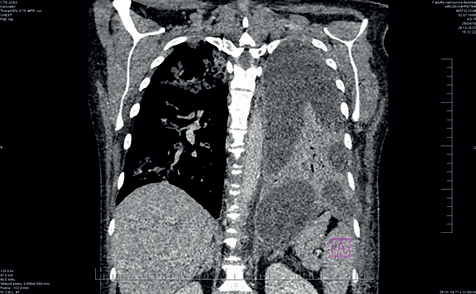

Obr. 1 Zánětlivý infiltrát v levé polovině hrudníku s fluidothoraxem, menší rozsah nálezu vpravo.Vstupní laboratorní hodnoty po přijetí byly následující: krevní obraz bez leukocytózy, ale s výraznou neutrofilií, 36 % neutrofilních tyčí, NLR (neutro/lymfo counts ratio) 18,5, C‑reaktivní protein (CRP) 360 mg/l, prokalcitonin (PCT) 4,9 mg/l, lehká elevace transamináz, GGT (gama‑glutamyltransferáza) 6,72 μkat/l, proto byly odebrány vzorky k sérologické diagnostice hepatitidy. V klinickém obraze však dominovala dušnost a hyposaturace při pozitivní DD (zvýšené hladině D‑dimerů). Následně bylo doplněno vyšetření pomocí CT angiografie plic, kde byl sice doložen nález bez známek plicní embolizace, byla však popsána zánětlivá konsolidace větší části levého dolního laloku, prchavé infiltráty i v centrální části všech laloků pravé plíce a levostranný fluidothorax. Z laboratoře byl hlášen slabě pozitivní pneumokokový antigen v moči, pacientka byla zajištěna empiricky ampicilinem s doxycyklinem. Z pěti lahviček hemokultur byl vykultivován Streptococcus pneumoniae, doxycyklin byl tudíž vysazen, antibiotická léčba byla deeskalována na krystalický peniclin G. PCR test výtěrem z nosohltanu opět potvrdil pozitivní Str. pneumoniae. Na zvolené terapii se klinický stav zlepšuje, průtoky kyslíku se snižují. V kontrolní laboratoři byla nově zjištěna výrazná leukocytóza s neutrofilií, hodnoty zánětlivých parametrů sice v poklesu – CRP 257,8 mg/l, PCT v normě, ale došlo ke zhoršení dušnosti a bolestí levé poloviny hrudníku. Rtg plic ze dne 27. října 2023 – zastření celého levého hemithoraxu – progrese výpotku (obr. 1); 28. října – zhoršení dušnosti. Zamýšlená hrudní drenáž pod ultrasonografickou kontrolou nebyla vzhledem k septaci výpotku provedena. Doplněno vyšetření výpočetní tomografií (CT) hrudníku s nálezem rozsáhlých septovaných tekutinových kolekcí (obr. 2) – po dohodě s pneumologem a chirurgem byla pacientka indikována k drenáži hrudním chirurgem. Do terapie byl přidán linezolid*. Dne 30. října byl pod sonografickou kontrolou zaveden hrudní drén v cca 6./7. mezižebří ve střední axilární čáře vlevo, drén odvedl žlutavou lehce kalnou tekutinu, celkem cca 1 500 ml, dne 31. října si pacientka drén zrušila; 31. října bylo provedeno kontrolní sonografické vyšetření hrudníku – laterálně v místě drénu lem tekutiny v podkoží, atelektatická plíce, bazálně z dorzální strany nad bránicí 20–30 mm lemu tekutiny, max. paravertebrálně, fibrinová vlákna.

Obr. 2 CT hrudníku – fluidothorax vlevo, septace výpotků v rozsahu celé plíce. CT – výpočetní tomografiePacientka se však zhoršila po stránce vědomí, celkově neklidná, nadále byla ponechána bez drenáže, byla zahájena dechová rehabilitace a do léčby přidány kortikoidy. Pro stav zmatenosti byl krystalický penicilin vysazen, nasazen ceftriaxon, pacientka na jednotce intenzivní péče tlumena kombinací midazolam + dexmedetomidin + klomethiazol. Ještě před nasazením kortikoidů se v krevním obraze objevuje narůstající trombocytóza – až 1 260 × 109/l, zahájena duální agregace. V dalším průběhu dochází ke zlepšení klinického stavu, HFNO (vysokoprůtoková aplikace kyslíku) se snižujícím průtokem. Dne 2. listopadu 2023 proběhlo kontrolní CT vyšetření s drenáží tekutinové kapsy, drén odvedl cca 120 ml serózní tekutiny, stav pacientky byl zlepšen, na oxygenoterapii nízkoprůtokovým kyslíkem brýlemi. Drén po odvodu menšího množství serózní tekutiny byl dále zrušen. Pro další vzestup hodnot aminotransferáz a amyláz byla rovněž ukončena terapie ceftriaxonem. Pokračuje dechová a pohybová rehabilitace, 7. listopadu byly pacientce zrušeny invazivní vstupy, 8. listopadu byla ukončena terapie linezolidem*, tudíž celkově byla účinná terapie podávána 21 dnů. Kortikoidy detrahovány. Kontrolním ultrazvukovým vyšetřením byl zjištěn výpotek mezi 16–21 mm, nevhodný k punkci, ponecháváme ke spontánní úpravě a observaci. Pacientka byla přeložena na standardní oddělení, kde bylo pokračováno v symptomatické terapii a rehabilitacích. Klinický stav byl zlepšen. V kontrolní laboratoři tendence úpravy jaterních obstrukčních enzymů, amylázy i lipázy, minimální vzestup hodnoty CRP bez klinické korelace. V krevním obraze trvající leukocytóza až 17 × 109/l pravděpodobně při kortikoterapii. Hodnoty trombocytů již skoro normalizovány, duální antiagregace ukončena. Pro epizodu asymptomatické tachykardie byl podán betablokátor. Pacientka byla již dále afebrilní, oběhově stabilizovaná, normosaturovaná. Byla propuštěna do domácí péče za ambulantních pneumologických kontrol.